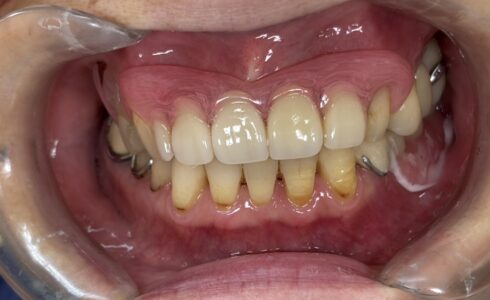

オールオンフォー シックス オーラルスキャン インプラント オールオンフォージルコニア スリーシェイプでデザイン 新CAM機導入で更に適合精度向上 2023.06.26 オールオンフォージルコニア スリーシェイプでデザイン 下顎オールオンフォージルコニア スリーシェイプでデザイン 下顎オールオンフォージルコニア スリーシェイプでデザイン 上顎オールオンフォージルコニア スリーシェイプでデザイン 新型CAM機で削り出し Tweet シェア オールオンフォージルコニア 新しいCAM機導入で更に... チタンオールオンフォーハイブリッド前装